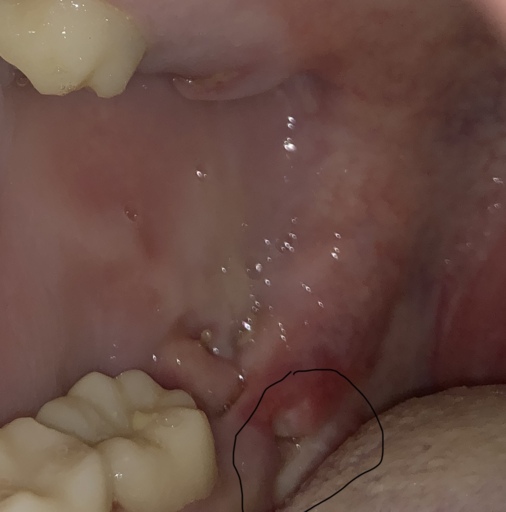

Gums where wisdom teeth were removed after 2 years seem to be suddenly opening again.

I had my wisdom teeth out almost 2 years aago. And just earlier I had noticed that I tasted slight blood in my mouth. I came to realize that where I had my wisdom teeth removed it seemed like it was starting to open back up again. It's slightly swollen and sore and it stings. Cannot get picture with where it is at

It is very unusual that the extraction sites would reopen after so many years. If this is only happening in one area, it may be a sign of a periodontal issue or it could be an issue with the tooth next to the extraction site. Bleeding in the mouth if not from trauma is usually an indication that there is an infection or disease present and should not be ignored. Schedule an appointment with your general dentist immediately or you can schedule a follow-up with the oral surgeon that treated you 2 years ago.

You need to seek the advice of a dental professional, preferably a periodontist or oral surgeon, who does this kind of work, and have him or her take an X-ray, either a CT scan or Panorex. The image should be not only of your teeth but also your jawbone. This will allow you to rule out any kind of infection, cyst, or problem at the extraction site that could account for the recurring swelling. It's possible that there's a problem with the tooth adjacent to the extraction socket. The tooth might have a cavity or need a root canal treatment, which would makes it feel as though it's affecting the socket area.